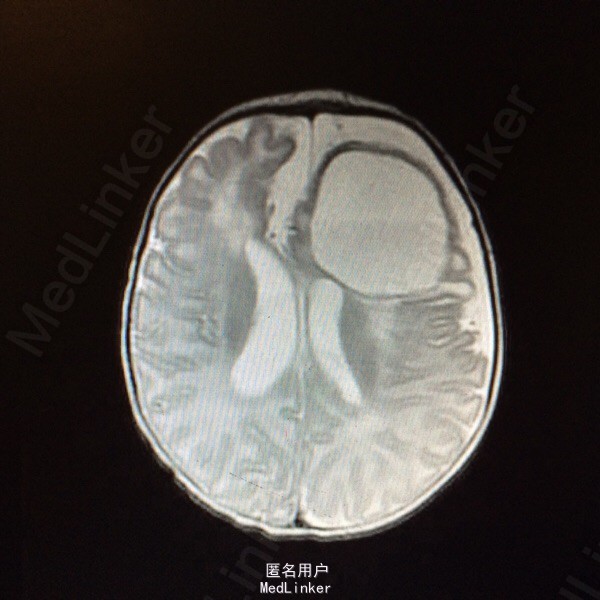

血常规:白细胞计数 WBC 18.61*10~9/L,中性粒细胞比例 Neu% 47.5%,淋巴细胞比例 Lym% 40.3%,血红蛋白 HGB 115g/L,血小板计数 PLT 433*10~9/L,CRP 79mg/L。大小便常规基本正常。肝肾功血糖心肌酶谱基本正常。降钙素原定量 PCT 1.80ng/ml。脑脊液生化 蛋白质 M-TP 528.1mg/灯笼,氯化物 CL 111.5mmol/L,葡萄糖 GLU 0.19mmol/L。 脑脊液常规检查(CSF) 细胞总数 110516.0×10~6/L,白细胞计数 108500.0×10~6/L,红细胞计数 2016×10~6/L,直接分类-单个核细胞比例 45%,直接分类-多核细胞比例 55%,颜色 黄色,透明度 浑浊,蛋白定性(Pandy's) 阳性(2+)。胸片:双肺改变考虑炎变,建议治疗后复查。颅内(彩超) :左侧脑实质囊性占位。磁共振增强扫描颅脑 :1、左侧额叶较大混杂信号囊状影,增强扫描壁明显强化,考虑脑脓肿;伴额、颞部蛛网膜下腔积液,请结合临床及其它检查。2、左侧侧脑室后角旁小结节影,增强扫描环形强化,考虑小脓肿可能。3、右侧侧脑室前角两处囊状影,未见强化,软化灶可能大,原因?PVL?